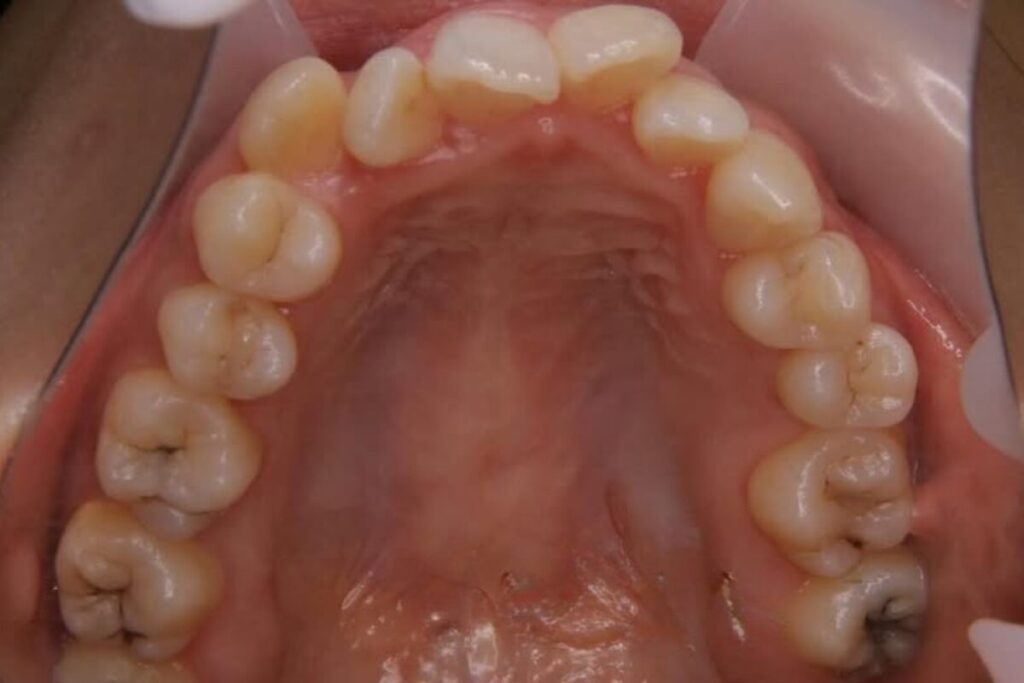

| 患者 | 28歳男性 |

|---|---|

| 主訴 | 歯ならびのガタガタ |

| 診断名 | UR7/LR7クロスバイトと上下叢生を伴うAngleⅠ級sk.1不正咬合 |

| 治療内容 | マウスピース型矯正装置(インビザライン)、部分的に上顎前歯部にワイヤー併用 |

| 抜歯の有無 | 非抜歯 |

| 治療期間 | 2年 |

| 費用(税込) | 594,000円 |

| リスクと副作用 | 痛み等、歯根吸収/歯肉退縮、後戻り、むし歯・歯肉炎の可能性。 |

【医師コメント】

上下のガタつきで来院された患者さんです。

精密検査の結果、UR7/LR7のクロスバイト(交叉咬合)と上下の叢生を伴う AngleⅠ級(sk.1)不正咬合 と診断しました。奥歯の前後関係はⅠ級で大きなズレは強くない一方、奥歯の噛み合わせのズレとスペース不足が原因でした。

治療はインビザラインを主体に非抜歯で計画し、歯列全体のバランスとかみ合わせの安定を意識しながら段階的に改善を進めました。

終盤、UL2のローテーションがわずかに残ったため、仕上げの精度を高める目的で上顎前歯部に部分的にワイヤーを併用しています。

治療は計画に沿って進行し、2年で歯列の配列とかみ合わせの改善を図ることができました。